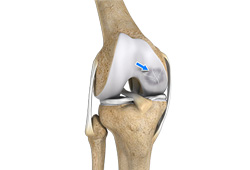

Chondral or Articular Cartilage Defects

The articular or hyaline cartilage is the tissue lining the surface of the two bones in the knee joint. Cartilage helps the bones move smoothly against each other and can withstand the weight of your body during activities such as running and jumping. Articular cartilage does not have a direct blood supply to it, so has less capacity to repair itself.

Articular Cartilage Injury

Patients with articular cartilage damage experience symptoms such as joint pain, swelling, stiffness, and a decrease in range of motion of the knee. Damaged cartilage needs to be replaced with healthy cartilage and the procedure is known as cartilage replacement.